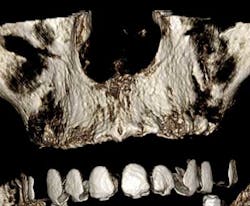

Finally, there is a product called Scaneez radiopaque markers that make radiographic guide creation instant and very inexpensive. Best of all, they create precise data points. These products use Stick ’n Scan technology to convert the patient’s existing denture to an instant radiographic guide — in seconds — in one visit — with no lab bills. The markers stick on and stick off. They are nontoxic and latex-free and are available at Suremark.com.